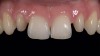

4. Bond/Seal Maintenance Risk Assessment

The fourth parameter is the risk of losing the bond or seal of the restoration to the tooth over time. Glass matrix materials, which are the weaker powder/liquid porcelains, and the tougher pressed or machined glass-ceramics absolutely require maintenance of the bond and seal for clinical durability.11,12 Due to the nature of the glass matrix materials and absence of a core material, the veneering porcelains are much more susceptible to fracture under mechanical stresses. Therefore, a good bond in combination with a stiffer tooth substructure (eg, enamel) is essential to reinforce the restoration. If the bond and seal cannot be maintained, then high-strength ce­ramics or metal-ceramics are the most suitable because these materials can be placed using conventional cementation techniques. Clinical situations in which the risk is higher for bond failure are: 1) moisture control problems; 2) higher shear and tensile stresses on bonded interfaces; 3) variable bonding interfaces (eg, different types of dentin); 4) material and technique selection of bonding agents (ie, as dictated by such clinical situations as the inability to achieve proper isolation for moisture control to enable the use of adhesive technology); and 5) the experience of the operator (Figure 4). An assignment of Low, Medium, or High Risk for bond and seal failure is based on the evaluated parameters.

Figure 4  Image of a preparation with a poor substrate and subgingival margins where maintaining the seal would be difficult. High-strength ceramics or metal-ceramics would be indicated.

Figure 4